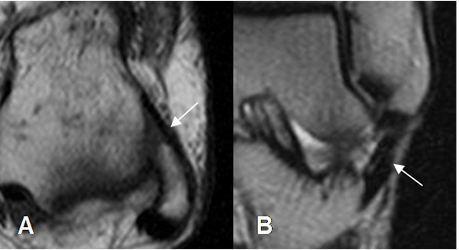

Fig 8. Ligamentos de la sindesmosis normal.

A y B: RM axial en T1. Ligamento tibioperoneo anterior (flecha delgada) y tibioperoneo posterior (flecha gruesa).

Fig 10. Ligamento peroneoastragalino anterior normal.

A: RM axial en T1 y B: RM coronal en T2.

Fig 11. Ligamento peroneoastragalino posterior normal.

A: RM axial en T1 y B: RM coronal en T1.